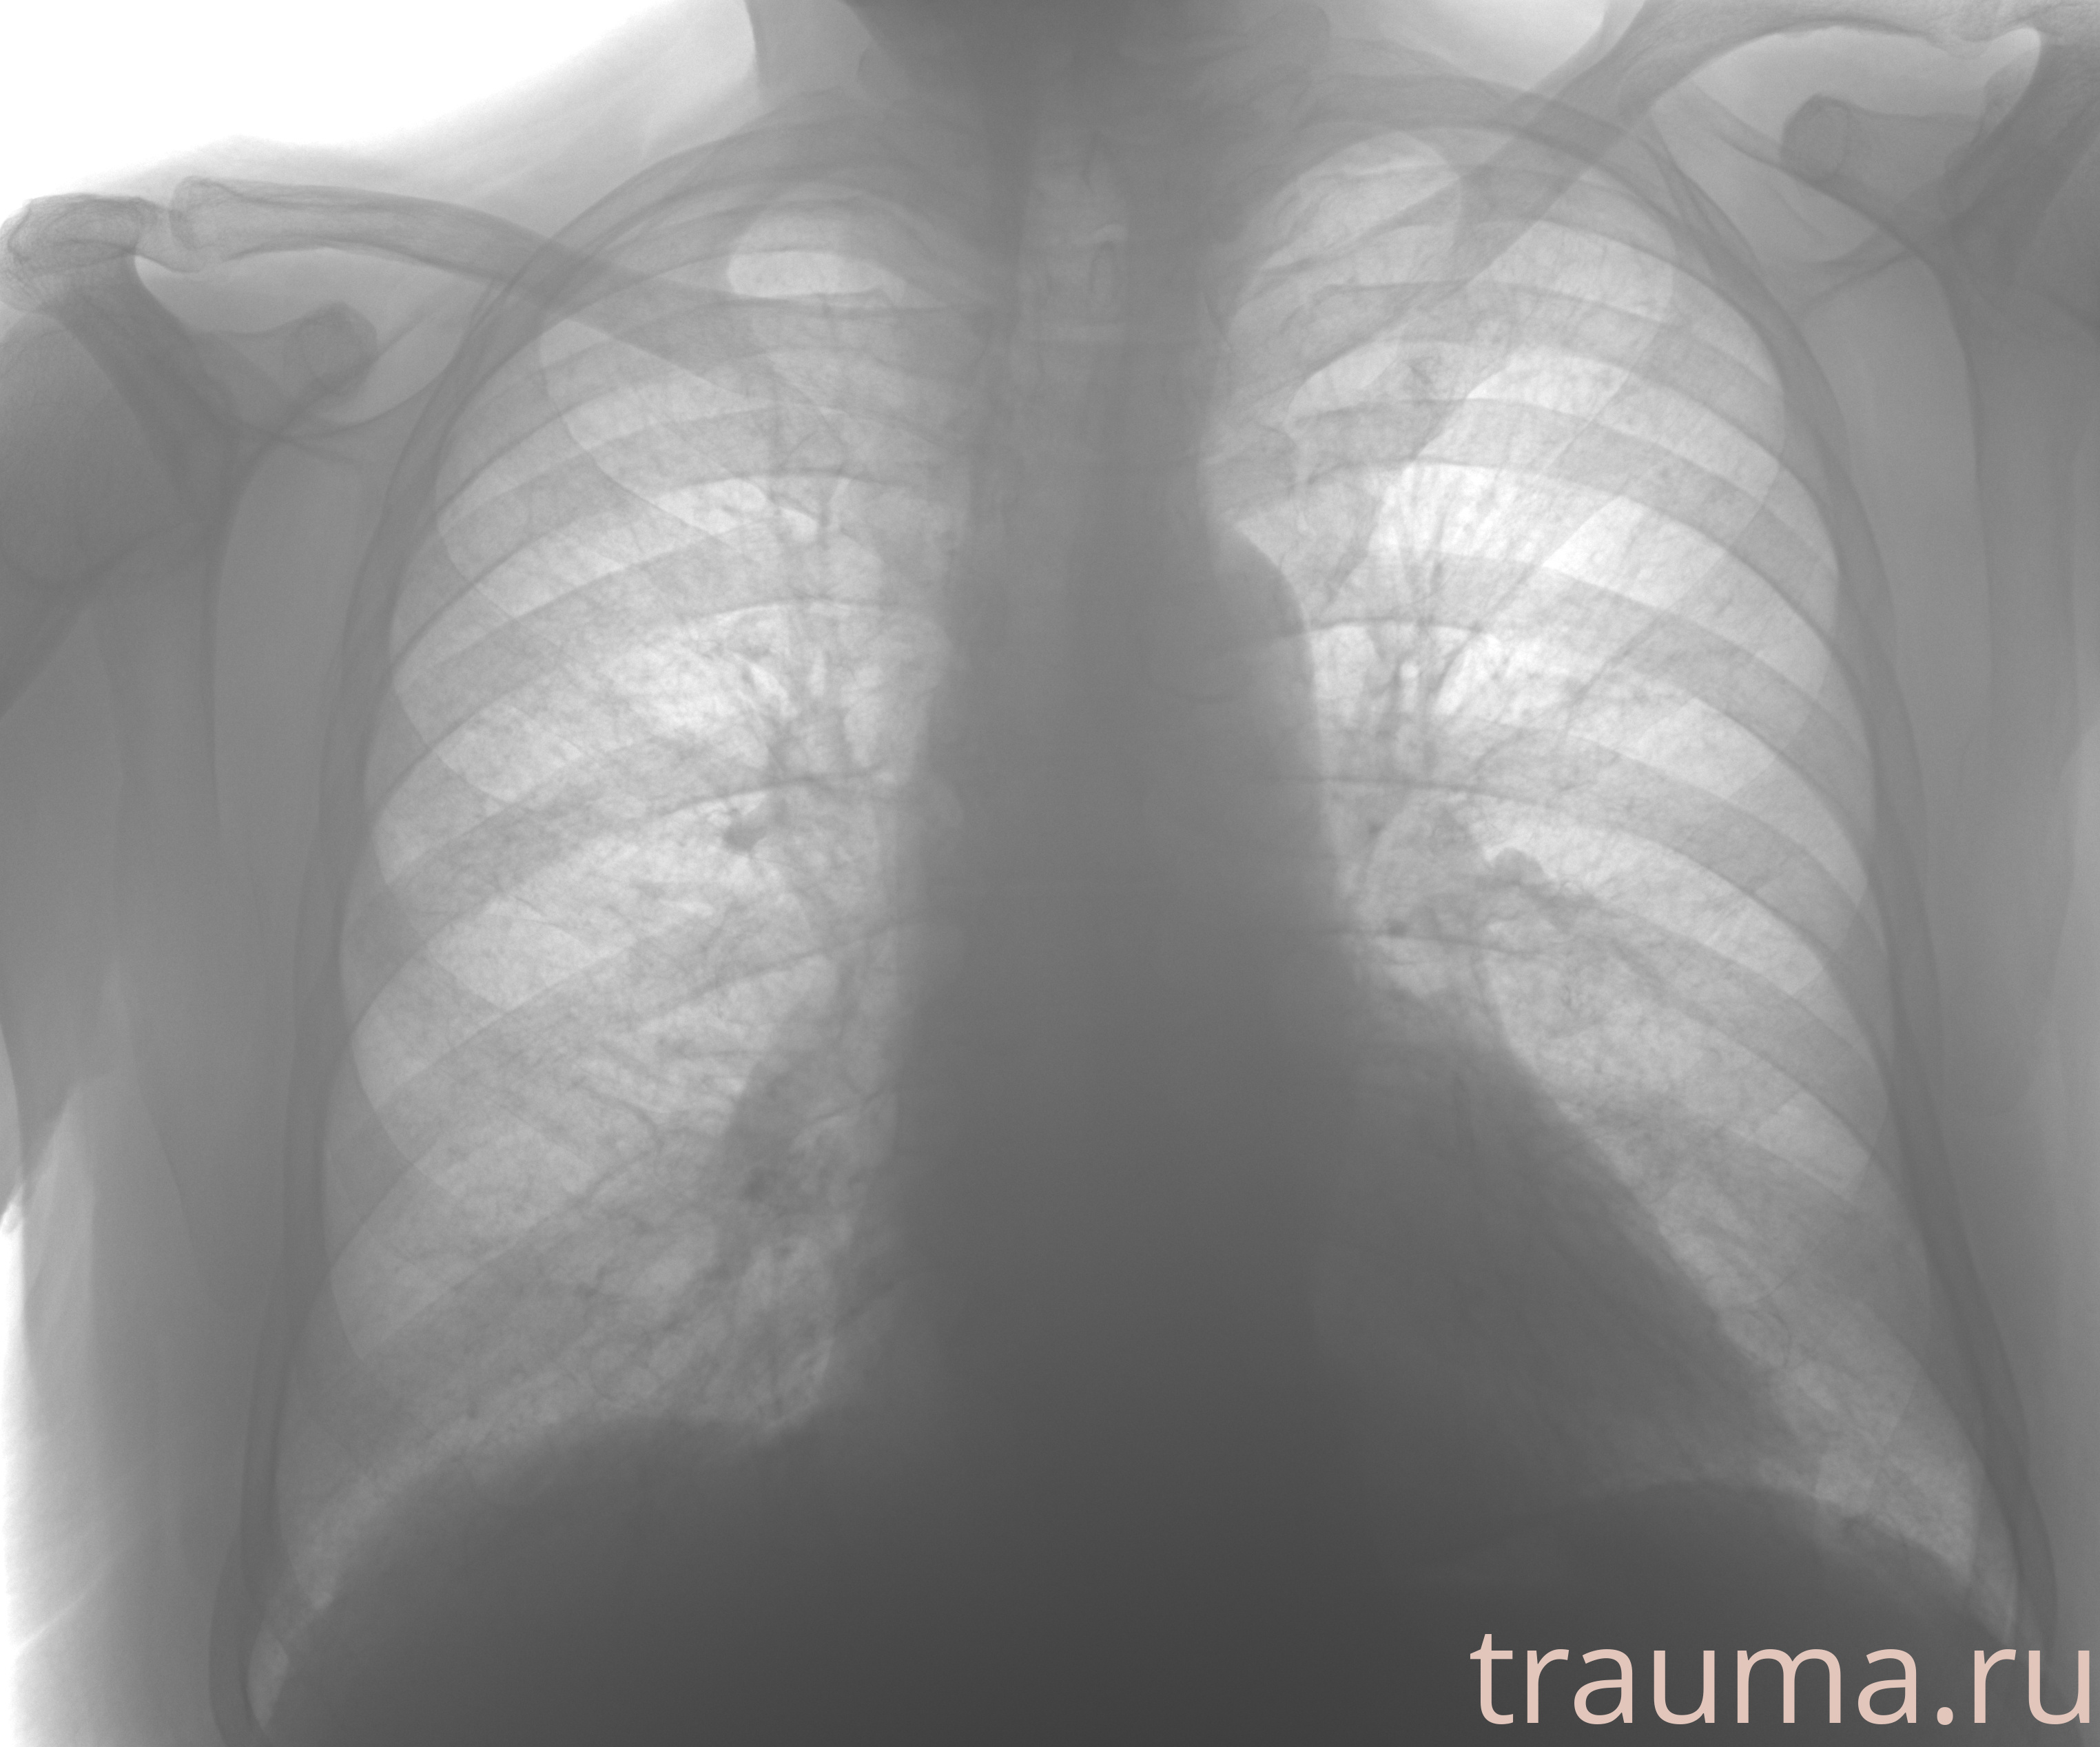

Рентгенограммы

Рентген на дому: по вашему адресу приезжает врач-рентгенолог, травматолог-ортопед с мобильным рентгеновским аппаратом, проводит диагностику травмы или заболевания, делает необходимые рентгенограммы, дает рекомендации по дальнейшему лечению. Получить качественные снимки в домашних условиях возможно благодаря уникальной методике, разработанной МосРентген Центром для института  Склифосовского

Яркость: 1   Контраст: 1   Инвертировать: 0 Увеличение: 1

Перетаскивайте мышь вверх/вниз для контраста, влево/право для яркости. Прокрутка колесом изменяет масштаб. Нажмите Сбросить для возврата к исходному изображению. При увеличении держите мышь в той области, которую хотите рассмотреть.

при переломе шейки бедра и пневмонии от компании МосРентген Центр - партнера Института имени Склифосовского